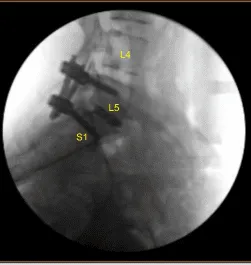

El autoinjerto morselizado seleccionado durante la descompresión, así como el aloinjerto morselizado, se canalizaban al interespacio con embudo y prensado, y luego el espaciador intersomal de titanio se tamponaba suavemente en el interespacio bajo guía fluoroscópica y se expandía hasta su posición correcta. La AP y la fluoroscopia lateral mostraron una posición adecuada.

A continuación, se realizó una tomografía computarizada adicional que mostró una posición ligeramente medial del alambre guía izquierdo de la L5. Por ello, se volvió a utilizar la navegación Jamshidi para volver a cenular el pedículo izquierdo L5 en una posición óptima. los tornillos pediculares canulados y navegados se colocaron sobre los cables K y se retiraron los cables K, con L5 y S1 a la izquierda logrando una instrumentación no segmentaria.

Estos se colocaban con insertadores en las lengüetas extensoras y tulipanes en tornillos pediculares bilaterales L5-S1 bajo guía fluoroscópica y se aseguraban con tapones de bloqueo que finalmente se apretaban con un dispositivo de par y antipar tras retirar los insertores. Se retiraron las tomas extensoras con el dispositivo automático. Hemostasis confirmada de nuevo.